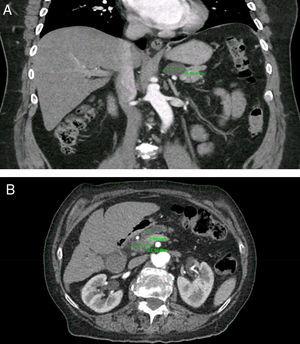

MRI revealed a septated pancreatic head cyst of 7 cm with a smooth capsule without lobulation and no connection to the pancreatic duct Surgery showed a low grade mucinous cystadenoma with ovarian stroma Mucinous cystadenoma CT images of a 30 year old female with a history of a biliary pancreatitis and cholecystectomy She had sudden increased left abdominal pain USEndoscopic ultrasound with fine needle aspiration is useful in pancreatic cysts smaller than 3 cm BMC Gastroenterol Dec 9; (1)413 doi /s Some doctors will elect to observe small pancreatic cysts (smaller than 2 cm) without malignant characteristics every six to 12 months with scans They will consider studying larger pancreatic cysts (more than 2 cm) and enlarging cysts with endoscopic ultrasound and at the same time may insert a needle into the cyst to obtain cyst fluid

For many patients, a pancreatic cyst — which may not be a true cyst but a pseudocyst that lacks the specialized cells that secrete fluid into the space they occupy — will go away without treatment Many doctors prefer to use a method called watchful waiting, where no treatment is given and the cyst is monitored for changes Often, a benign cyst will resolve within six weeks and no Serous cystadenomas are benign focal cystic lesions which usually include multiple, small (12 cm in diameter) cysts separated by thick fibrous septa, resembling a honeycomb (Fig 4) They can be located anywhere in the pancreas and are rarely malignant, opposite to IPMNs and mucinous cysts Lymphoepithelial cysts are very rare cystic lesions of the pancreas They usually measure less than 5 cm and are seen in men The cysts are lined by squamous epithelium and surrounded by dense lymphoid tissue Their imaging appearances vary and they may be either unilocular or multilocular